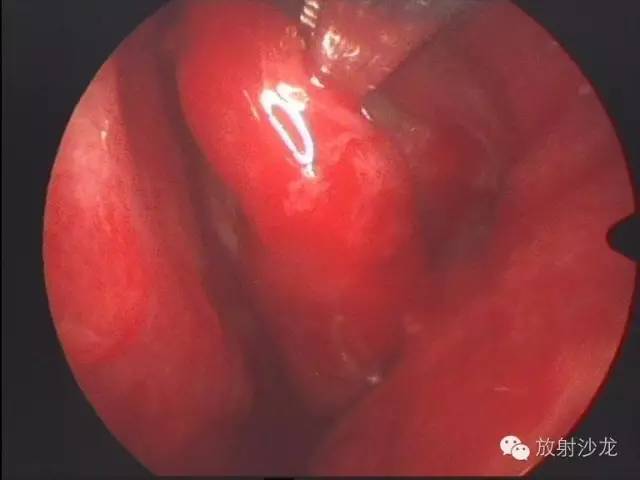

【术中鼻内镜】